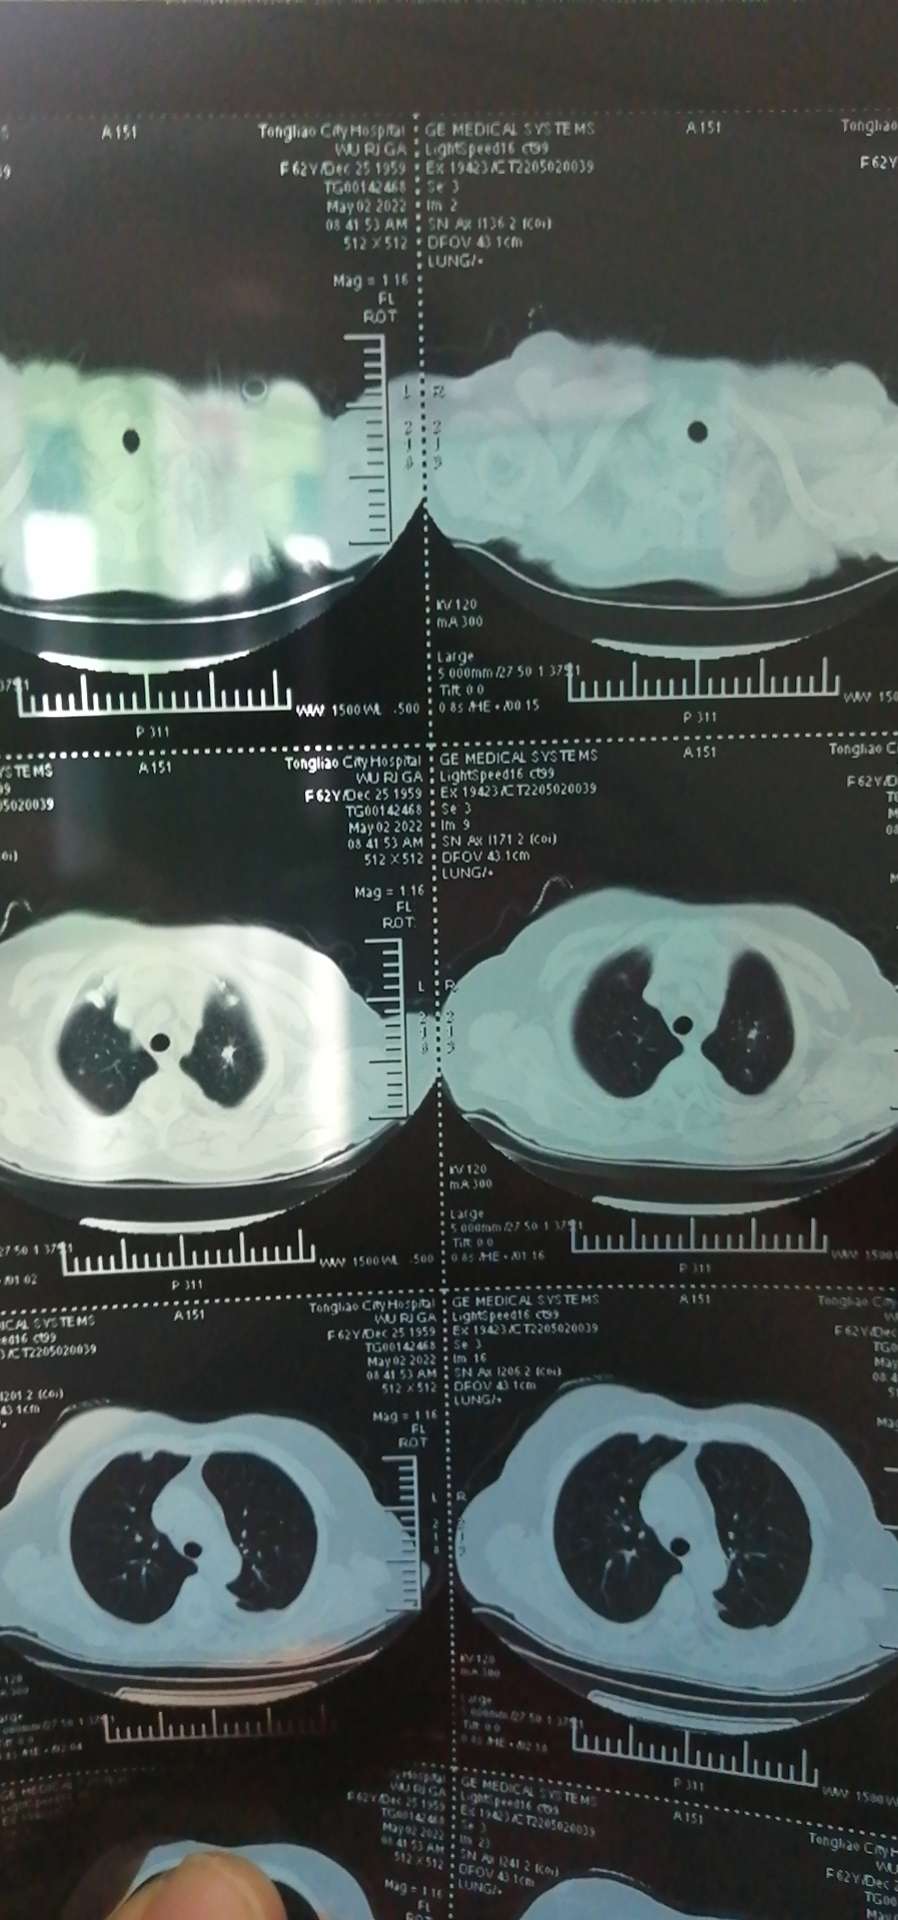

隔80天的复查,

因为疫情,只能在当地做了平扫!医生说Ct没什么变化,但是CEA在缓慢升高。医生说还在正常范围,不用太在意!

补发影像片